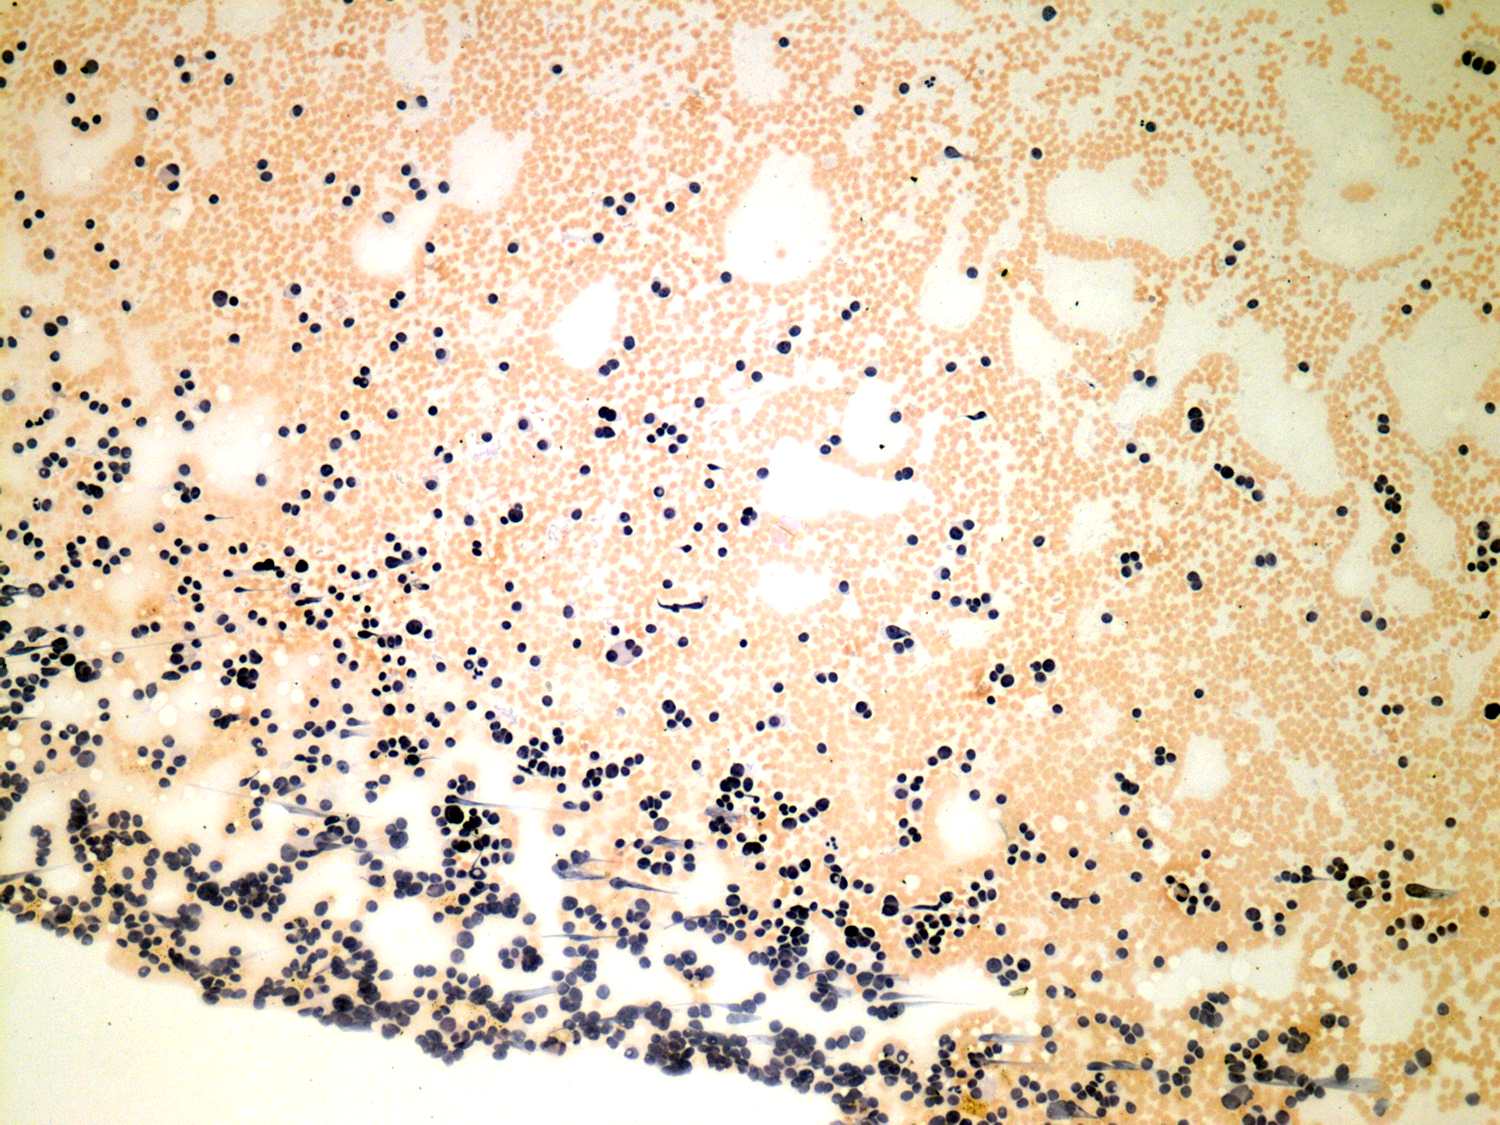

Second examination 4 years later (cytologic picture 1)

Pap-smear, 100x. There is no colloid in the background. Cells occur dispersed.